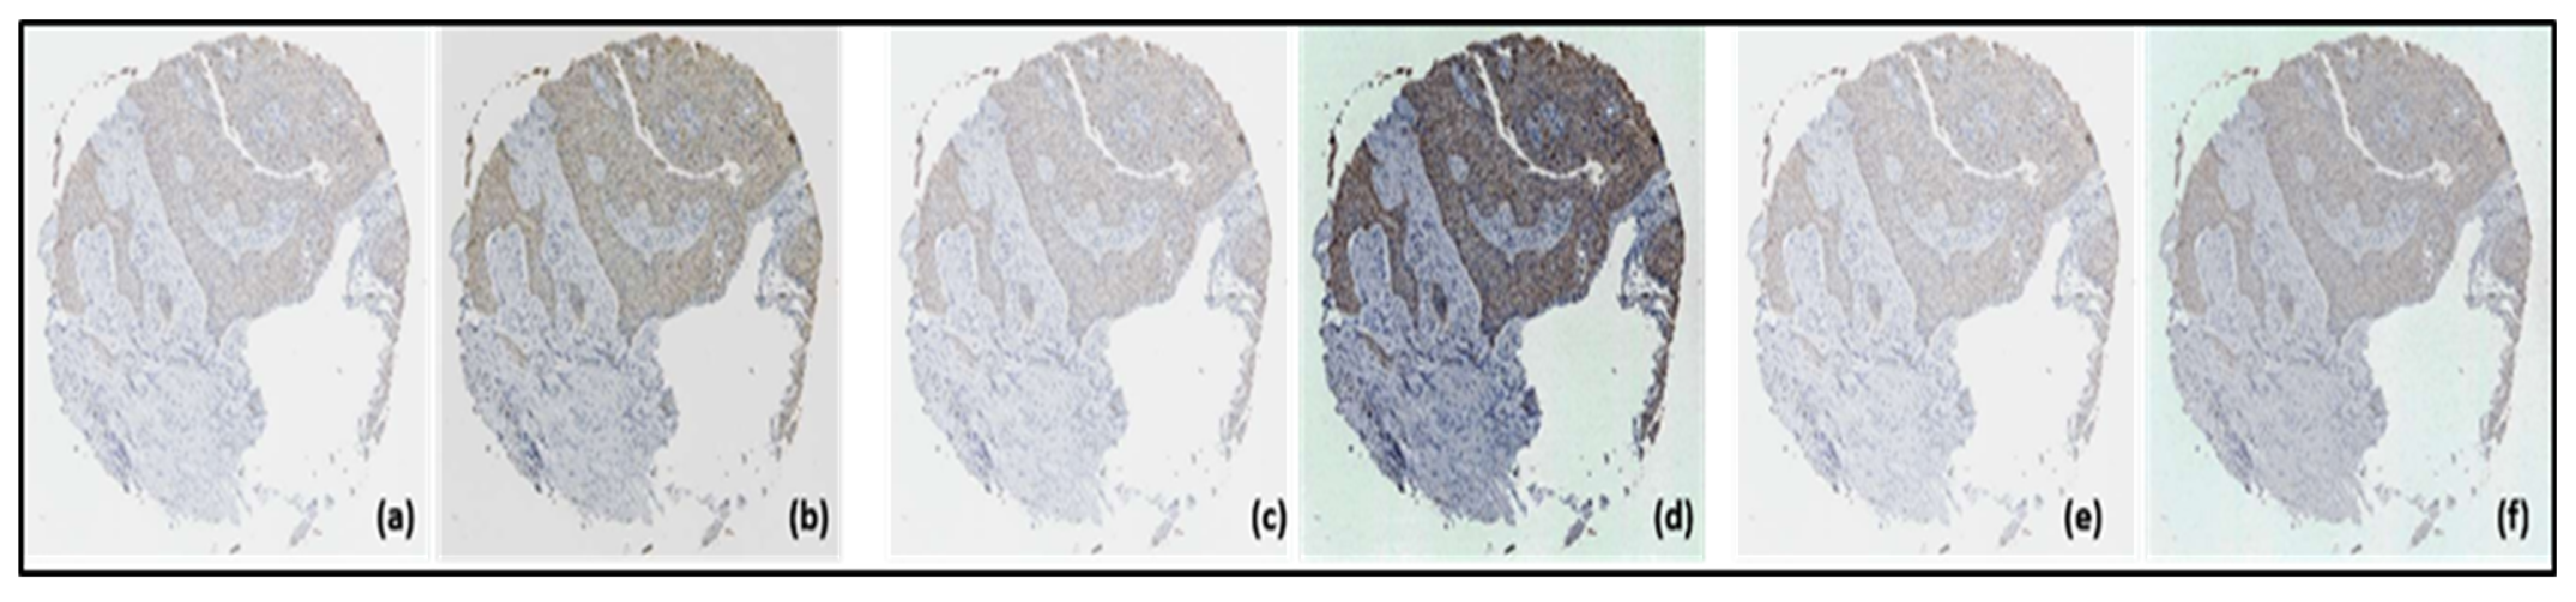

3.1. SLIC Super Pixels

3.4. Segmented Images